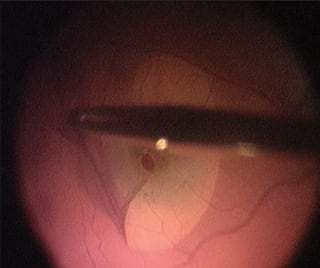

Eyes with proliferative vitreoretinopathy often have surface ERMs that may not be visible, especially on the surface of detached retina. Staining with Membrane Blue makes these peripheral ERMs and starfolds clearly visible and amenable to removal (Figure 2). The more complete the ERM removal, the greater the chance of long-term retinal reattachment in proliferative vitreoretinopathy surgery.

Figure 2. Stained epiretinal membrane at the apex of a retinal starfold grasped with intraocular forceps.